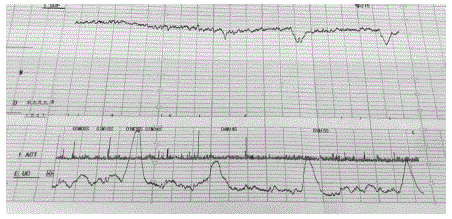

Gestante, 32 anos de idade, secundigesta com uma cesárea anterior, 40 semanas e 2 dias de gravidez. Refere contrações irregulares e redução de movimentação fetal há 1 dia. Ao exame clínico, bom estado geral, corada, PA 120x70mmHg, altura uterina 30 cm, BCF presente rítmico. Toque vaginal com colo grosso, posterior, impérvio.

Vitalidade fetal: tônus adequado, movimentação corpórea e respiratória presentes, índice de líquido amniótico de 4,2 cm. Cardiotocografia apresentada.

Qual é a conduta adequada neste momento?